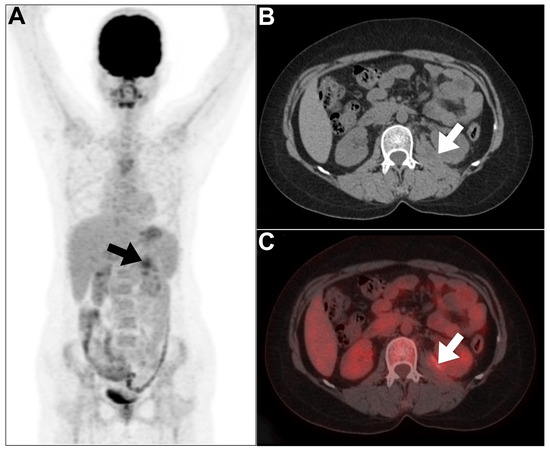

- Pijl, J.P.; Glaudemans, A.W.; Slart, R.H.; Kwee, T.C. 18F-FDG PET/CT in autosomal dominant polycystic kidney disease patients with suspected cyst infection. J. Nucl. Med. 2018, 59, 1734–1741. [Google Scholar] [CrossRef]

- Ronsin, C.; Bailly, C.; Le Turnier, P.; Ville, S. Value of FDG-PET/CT in monitoring cyst infections in patients with autosomal dominant polycystic renal disease. Clin. Kidney J. 2021, 14, 2273–2275. [Google Scholar] [CrossRef]

- Bobot, M.; Ghez, C.; Gondouin, B.; Sallée, M.; Fournier, P.-E.; Burtey, S.; Legris, T.; Dussol, B.; Berland, Y.; Souteyrand, P. Diagnostic performance of [18F] fluorodeoxyglucose positron emission tomography–computed tomography in cyst infection in patients with autosomal dominant polycystic kidney disease. Clin. Microbiol. Infect. 2016, 22, 71–77. [Google Scholar] [CrossRef]